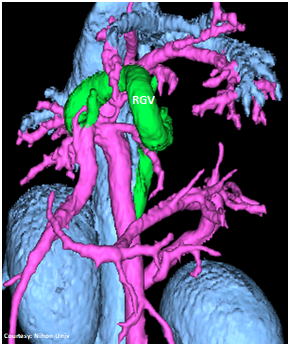

Does the RIGHT GASTRIC VEIN (RGV) contribute blood to the shunt?

WEISSE 2022

slide11